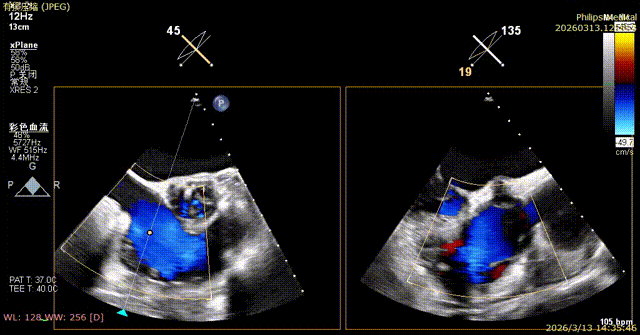

Comparison of Tricuspid Annular Area After Annuloplasty

Preoperative tricuspid annular area: 15.6 cm²

Postoperative tricuspid annular area: 7.68 cm²

Following annuloplasty, leaflet coaptation was improved compared with the preoperative state, and regurgitation was reduced from severe to trivial.